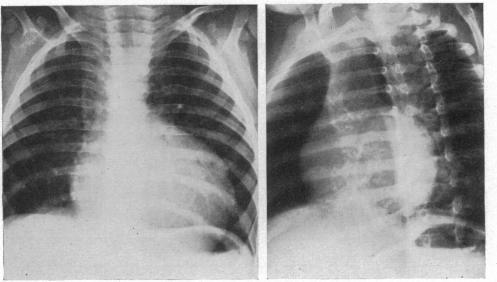

Congenital tricuspid atresia.

Br Heart J. 1953 Jul;15(3):287-97. doi: 10.1136/hrt.15.3.287.